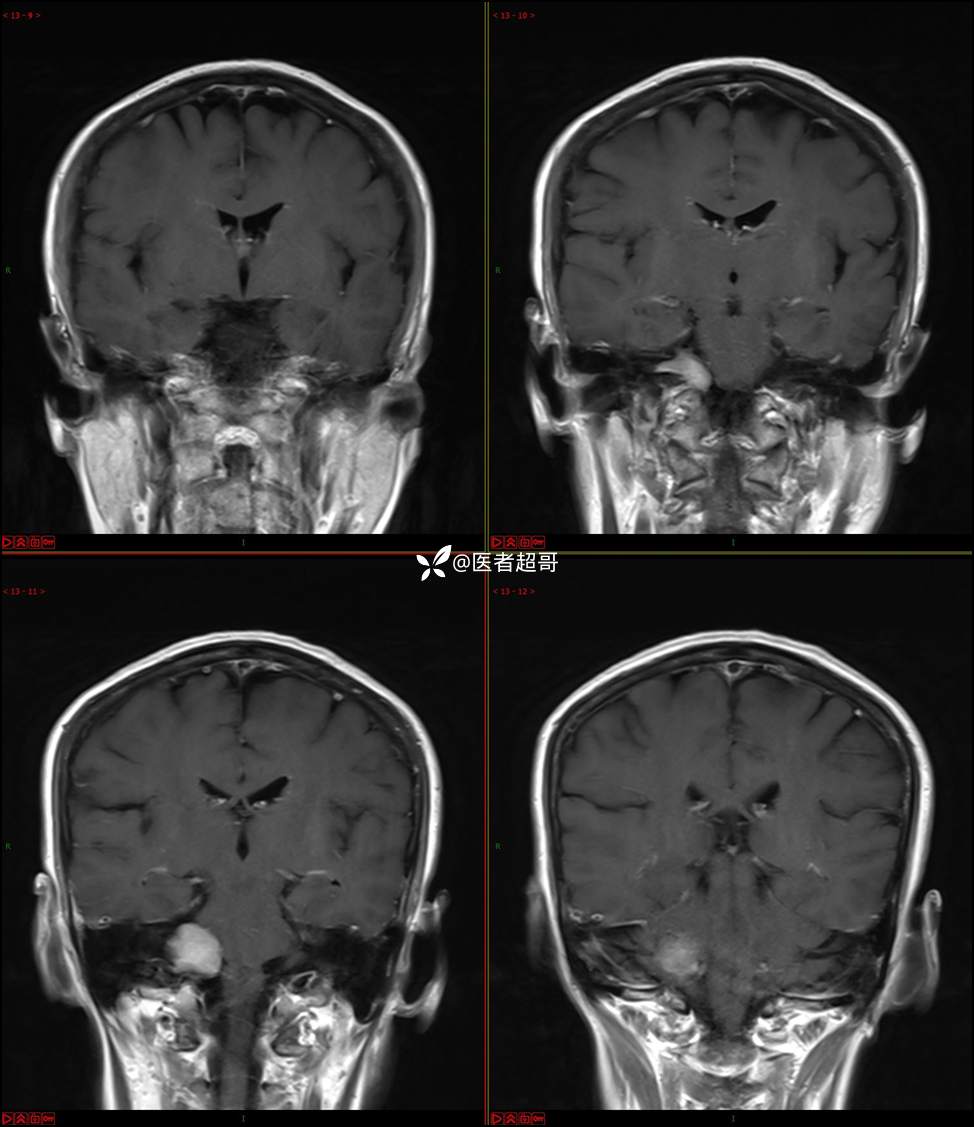

CPA区占位,是鞘瘤?脑膜瘤?请赏析!

主 诉:耳鸣3年,头晕伴恶心4天。

现病史:患者3年前出现耳鸣,蝉鸣音,反复发作,夜间自觉明显,于2018年8月至我院耳鼻喉科就诊,行颅脑CT检查未发现明显异常改变,给予对症处理(具体不详);4天前突发头晕,伴明显恶心,至市人民医院就诊,行颅脑CT未见明显异常,颅脑MRI发现右侧桥脑小脑角区占位性病变。本次发病来无明显头痛,无肢体抽动,无大小便失禁。为求进一步诊治,遂来我院门诊,以“听神经良性肿瘤”收住入院。发病来,患者神志清,精神可,二便正常,饮食可,睡眠不佳,近期体重无明显变化,否认癫痫发作病史。